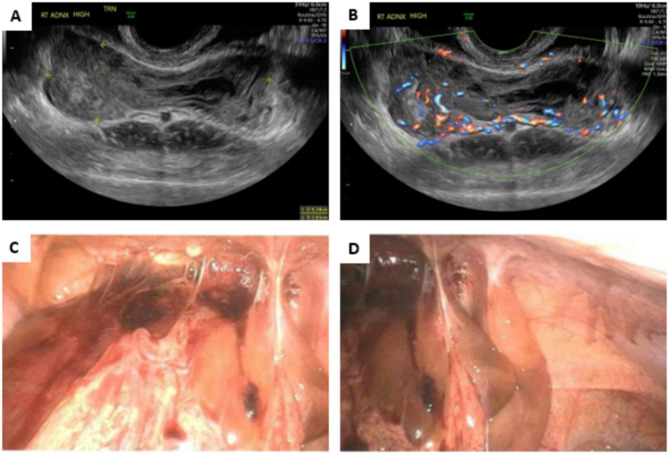

MEIS1::NCOA1/2 fusions have been identified in spindle cell tumors of the gynecologic and genitourinary tracts, as well as in two cases of intraosseous spindle cell rhabdomyosarcomas. These tumors typically exhibit an infiltrative growth pattern characterized by short fascicles of monomorphic, plump spindle cells. Their immunoprofile is nonspecific, often demonstrating focal and variable expression of ER, PR, CD10, and cyclin D1. Depending on their location, these tumors are frequently diagnosed as low-grade endometrial stromal sarcomas or undifferentiated uterine or renal sarcomas. While they generally exhibit low malignant potential with multiple local recurrences, two cases with high-grade morphology and lung metastases have been reported. Here, we describe a case of pelvic low-grade spindle cell sarcoma in a 19-year-old woman characterized by strong diffuse ER/PR expression and focal CD10 positivity. Next-generation sequencing revealed a MEIS1::NCOA1 fusion without additional genetic alterations. She presented with extensive local disease throughout the abdomen, while the uterus and adnexa appeared normal intraoperatively.